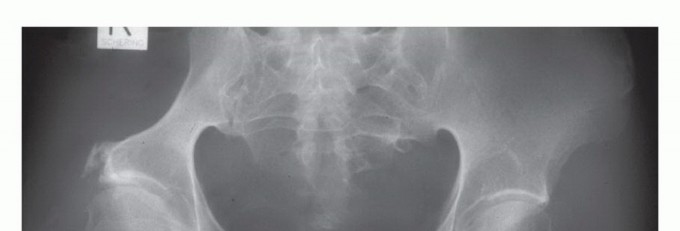

- الأشعة السينية (X-rays): هي الفحص الأولي، ويمكن أن تكشف عن التغيرات العظمية مثل التآكل أو التصلب أو الكسور.

- التصوير المقطعي المحوسب (CT Scan): يوفر صورًا مقطعية مفصلة للعظام والأنسجة الرخوة، ويساعد في تحديد حجم الورم، مدى انتشاره داخل العظم، وعلاقته بالهياكل المحيطة.